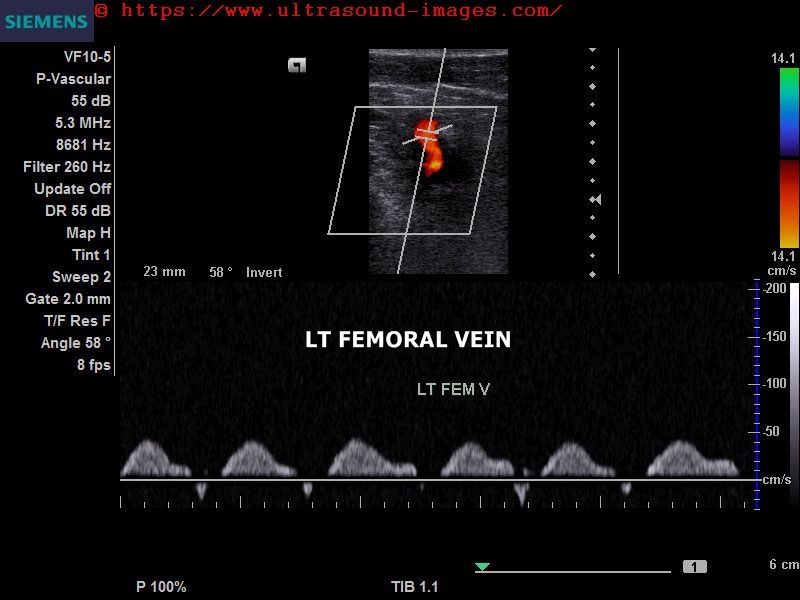

This middle-aged female patient presented with left calf pain and tenderness of a few days duration. She underwent medical treatment for a few days but has persistent mild calf pain. Colour Doppler and spectral Doppler ultrasound revealed normal flow augmentation and compressibility of the left femoral vein. However, the left popliteal vein, shows lack of flow in the lower half , suggesting left popliteal vein thrombosis. spectral Doppler ultrasound showed absent waveform and this was confirmed on colour Doppler ultrasound showing lack of flow signal in the lower half of the left popliteal vein. Thus, this colour Doppler ultrasound study confirms left popliteal vein thrombosis.

normal flow is observed in the deep veins of lower left leg, namely the anterior tibial, posterior tibial and peroneal veins.

Surprisingly, some flow signal was seen in the left popliteal vein on probe pressure and release; this was also seen on eliciting augmentation by pressure below the left calf. This suggests, that the left popliteal vein thrombosis maybe only partial, with some degree of recanalisation following medical treatment ( meaning thrombolysis).